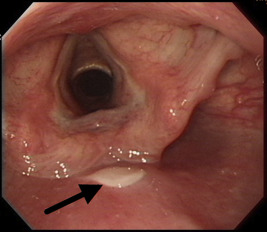

The patients medical history was unremarkable. She did not take any drugs, antibiotics, or caustic material in the past few months. She also denied symptoms of esophageal reflux, acid regurgitation, and epigastric pain. She had no fever. She also had not previously received any medical procedure. On presentation, her vital signs were stable. A physical examination showed no specific abnormality at the head and neck, chest, or abdomen. The patients hemogram, biochemical levels, and cardiac markers were all normal. The chest radiograph and electrocardiogram also appeared normal. She received upper endoscopy in the afternoon on the same day, which showed longitudinal, whitish membrane detached from the posterior wall of the hypopharynx extending to the middle esophagus (30 cm from incisors), which looked like a wrinkled deflated balloon surface (Figure 1 ; Figure 2 ). Unlike infective disease, the lesion was single and regional without ulcerative surface, exudates, or bleeding. The patient’s clinical history and endoscopic scald burn-like mucosal lesion supported the diagnosis of esophageal thermal injury. We did not perform biopsy to avoid further mechanical mucosal injury and bleeding because friable mucosa underneath the detached membrane was seen during the endoscopic procedure. We treated the patient with an oral form of proton pump inhibitor [lansoprazole (30 mg) q.d.] to decrease reflux acid-related injury and educated the patient to eat a cool liquid diet temporally. Three days later, dysphagia and odynophagia improved well and the patient resumed a normal diet. One month later, she was totally free of the aforementioned symptoms. She refused repeat endoscopy and received double-contrast esophagogram 2 months later, which showed normal finding without stricture or remarkable mucosal lesion. The proton pump inhibitor was discontinued after the esophagogram.

Figure 1. Endoscopic view of the pharynx with a longitudinal membranous lesion at the posterior wall of the hypopharynx. |

Esophageal thermal injury can cause odynophagia, dysphagia, and chest discomfort, but it is rarely considered in the list of causes at initial presentation. In our case, the relevant history and endoscopic finding and rapid clinical recovery support the diagnosis of acute reversible esophageal thermal injury caused by hot food intake. The typical endoscopic finding of esophageal thermal injury is “candy-cane esophagus”, which is characterized by alternating white and red linear mucosal bands [1] . In 2005, Choi et al [2] reported a case of esophageal thermal injury caused by ingestion of hot tea in a 38-year-old woman who underwent upper endoscopy 8 days, 12 days, and 2 months after the onset of odynophagia. Serial endoscopy mainly showed a whitish pseudomembranous lesion in the beginning, which became more similar to the candy-cane appearance 4 days later and finally healed without stricture 2 months later. The authors postulated that during the healing process of esophageal thermal injury, bullae became the whitish pseudomembrane and then presented with the typical candy-cane appearance. In 1996, Javors et al [4] described an esophageal intramural blister that developed after eating hot lasagna. The blister was outlined by a double-contrast esophagogram 5 days after the onset of odynophagia. This report documented the acute bullae formation stage of esophageal thermal injury. In our case, we conducted endoscopy 1 day after the onset of symptoms and the endoscopic finding revealed a linear, ruptured bullae-like lesion. This is the early endoscopic finding of esophageal thermal injury caused by ingesting hot food among the several reported cases [1] ; [2] ; [3] ; [4] ; [5] ; [6] ; [7] .

A literature review of reported cases indicated that the endoscopic manifestation of esophageal thermal injury is decided based on the nature of hot food (liquid or solid), ingestion amount, acute or chronic episodes, and timing of endoscopy after the injury. The sequences of esophageal thermal injury are as follows: a scald injury resulting from mucosal erythema, followed by bullae or blister formation, rupture and necrosis of the mucosa with pseudomembrane, then ulcer with exudate or fragile mucosa, and finally healing with fibrosis. Because we performed upper endoscopy within 24 hours after the onset of the symptoms, the findings of our case only showed a longitudinal, whitish membrane lesion, which was comparable to that of the early stages of the injury with bullae formation. Another category of esophageal thermal injury is caused by radiofrequency catheter ablation of left atrial arrhythmia [8] . The endoscopic findings of this kind of esophageal thermal injury vary from focal erythematic change to focal ulcer. According to Halm et al [8] , esophageal damage may develop if intraluminal temperatures reach ≥41°C.